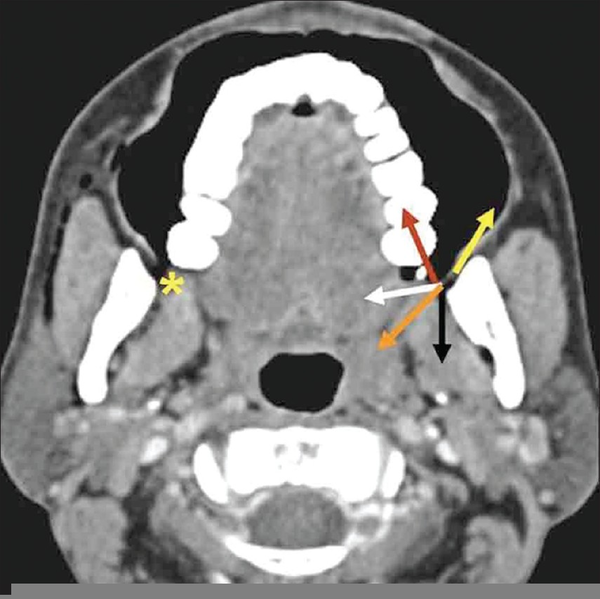

Axial drawing of the left retromolar trigone region. The relationship What Is Retromolar Trigone the retromolar trigone is a challenging transoral surgical site due to the difficulty of visualization. the retromolar trigone, sometimes called the retromolar fossa, is an oral cavity subsite that consists of the. retromolar trigone (rmt) is a rare location for oral cavity cancers. retromolar trigone (rtr) is the gingiva or mucosa covering the alveolar ridge posterior. What Is Retromolar Trigone.